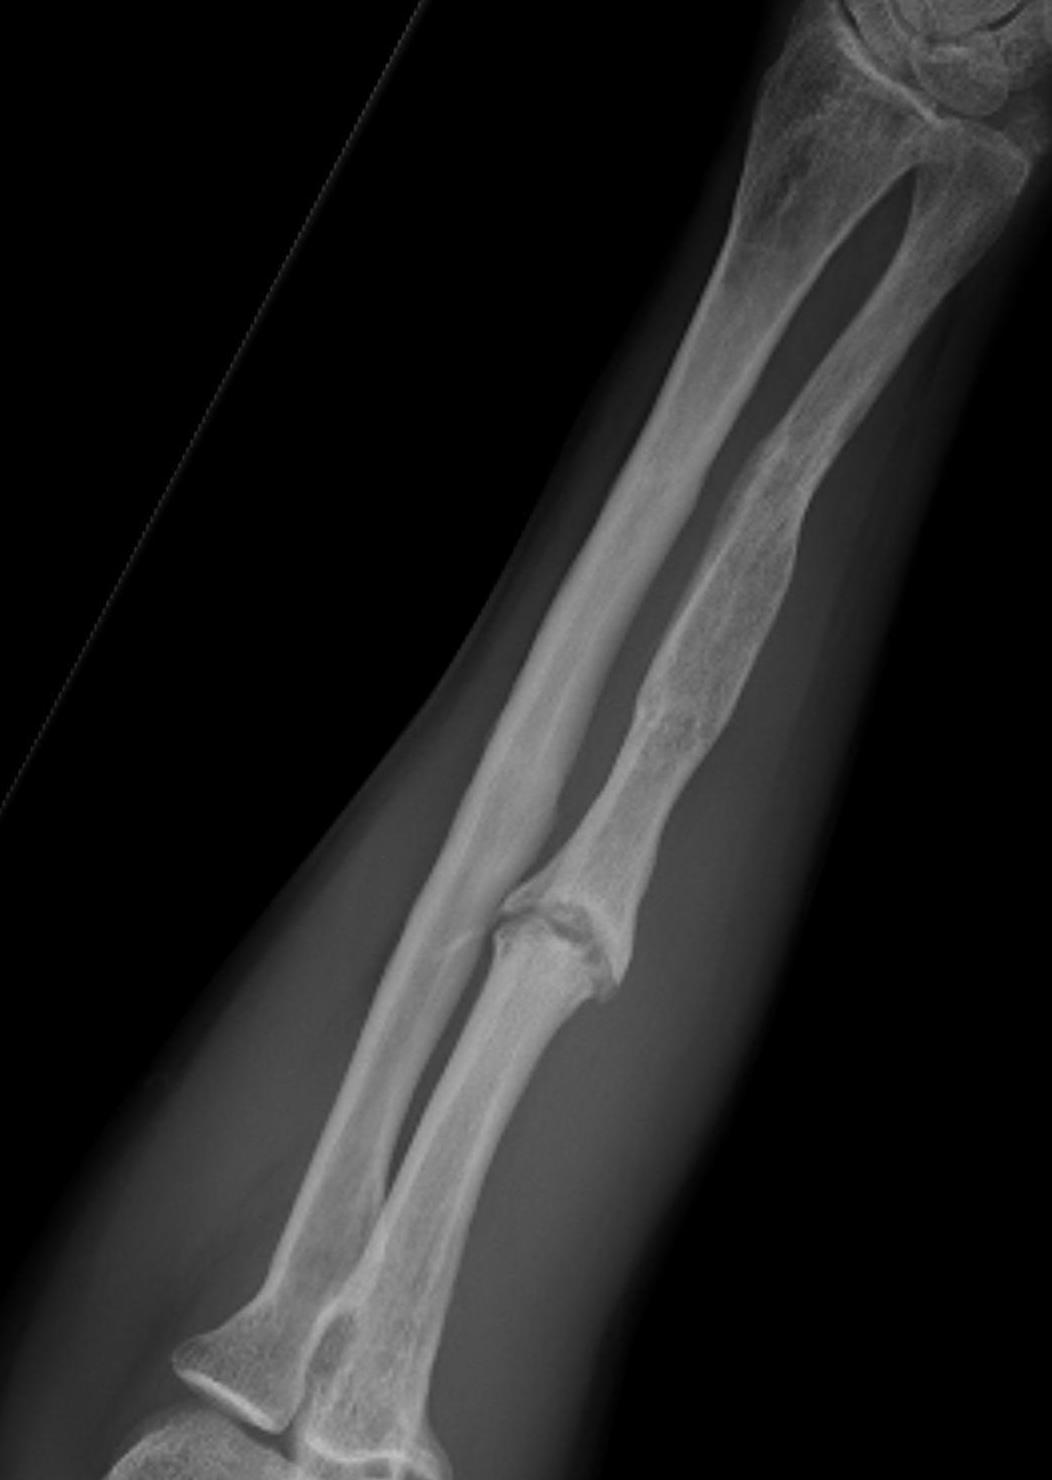

Night stick injury - direct blow or trauma to ulna

Distal 1/3

Midshaft / middle 1/3

Proximal - beware Monteggia / radial head dislocation